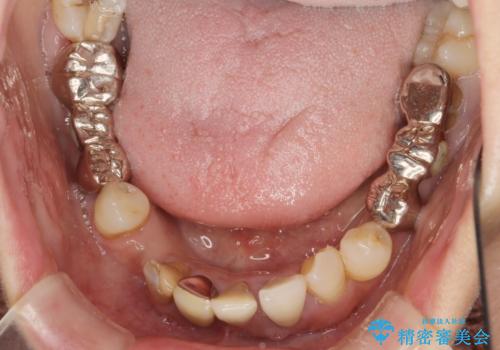

歯周病 全顎治療

- 前歯の見た目、入れ歯による噛めないことの改善を求めて来院されました。

検査により全顎的な歯周病治療、欠損のインプラント補綴、根管治療が必要な状態であることをお伝えし、治療を計画します。